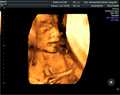

乌海市妇幼保健院是内蒙古自治区西部地区可以开展人类辅助生殖技术的医疗机构,可开展的项目主要包括夫精人工授精、体外受精-胚胎移植、卵胞浆内单精子显微注射三项技术,并积极推行不孕不育症及生殖内分泌疾病的规范化诊断,是乌海市重要的生殖机构。

乌海市妇幼保健院[1]的生殖医学科于2008年脱胎于内分泌不孕不育科,在2014年内蒙古自治区卫生和计划计划生育委员会批准我院筹备开展人类辅助生殖技术,2016年1月通过国家级专家组的试运行评审,而后正式运行评审。